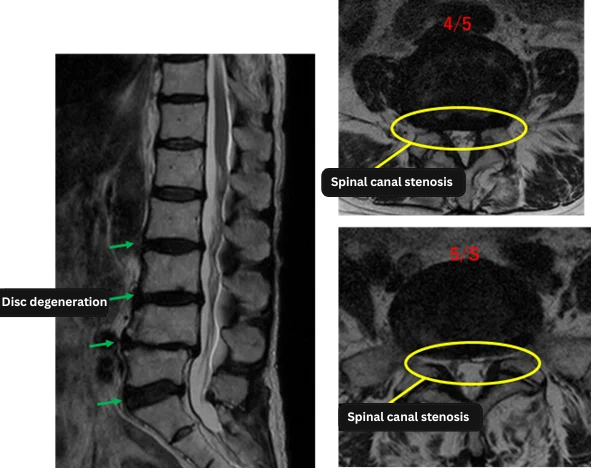

Imaging and findings

| Level | Findings |

| L1/2 | Normal |

| L2/3 | Degeneration |

| L3/4 | Degeneration, bulging |

| L4/5 | Degeneration, bulging, left foraminal stenosis |

| L5/S | Degeneration, bulging, bilateral foraminal stenosis |

The above findings were also observed on the imaging.

Findings indicate disc degeneration and foraminal stenosis at L3/4, L4/5, and L5/S,

which are considered the most likely causes of the patient’s symptoms.